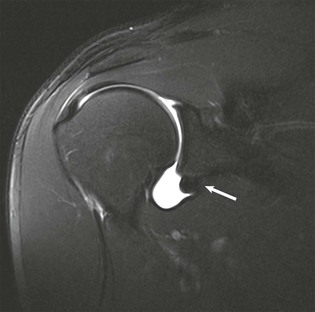

Denervation of a rotator cuff muscle can result from either a compressive neuropathy or an acute traumatic injury of a nerve. Compressive neuropathies most commonly result from a paralabral cyst associated with a labral tear, but they can also be caused by fractures or other masses in the area of the shoulder (see Fig. 44-23, A and C). Paralabral cysts (Fig. 44-28) most commonly arise in association with a SLAP tear or a posterior labral tear. These cysts may extend into either the suprascapular notch or the spinoglenoid notch and can result in entrapment of the suprascapular nerve, which innervates the supraspinatus and infraspinatus muscles.115 Paralabral cysts arising from an anteroinferior labral tear are less common, but they may compress the axillary nerve as it traverses the quadrilateral space.116 Compression of the axillary nerve can also result from adhesive bands in the quadrilateral space in athletes, such as pitchers, who participate in repetitive overhead activities.117 The axillary nerve innervates both the teres minor and deltoid muscles. Anterior dislocation can result in a stretching injury of the axillary nerve and give rise to a temporary or permanent denervation of the teres minor and deltoid muscles and can occasionally mimic a rotator cuff tear on clinical examination in a person with previous anterior dislocation. Denervation atrophy initially results in edema of the affected muscles and over time will progress to an irreversible fatty replacement. On MRI, acute denervation edema appears as a high T2-weighted signal within the affected muscle and is associated with reversible muscle atrophy (Fig. 44-29). The more chronic and irreversible form of fatty atrophy appears as decreased muscle bulk and bright streaks (representing the fat) within the muscles on T1-weighted images (see Fig. 44-23).

A wide variety of glenolabral lesions exist, and in a given patient, the specific lesion depends on the mechanism of injury that led to the labral abnormality. Unidirectional instability may be further classified as anterior or posterior in direction. Anterior glenohumeral instability usually results from a fall on the outstretched arm or stress while in abduction and external rotation. In patients younger than 35 years, the typical lesion resulting from an anterior dislocation is either a Bankart lesion or a Bankart variant. In the patient older than 35 years with a first-time anterior shoulder dislocation, the resulting lesion is usually either a tear of the supraspinatus tendon, a tear of the subscapularis tendon, or an avulsion injury of the greater tuberosity of the humeral head. Posterior instability occurs less commonly than anterior instability and can result either from a single traumatic event resulting in posterior dislocation of the humeral head or from repetitive microtrauma as occurs in weight lifters, football linemen, and swimmers. Finally, a miscellaneous category of lesions includes the SLAP tear and internal impingement syndrome.